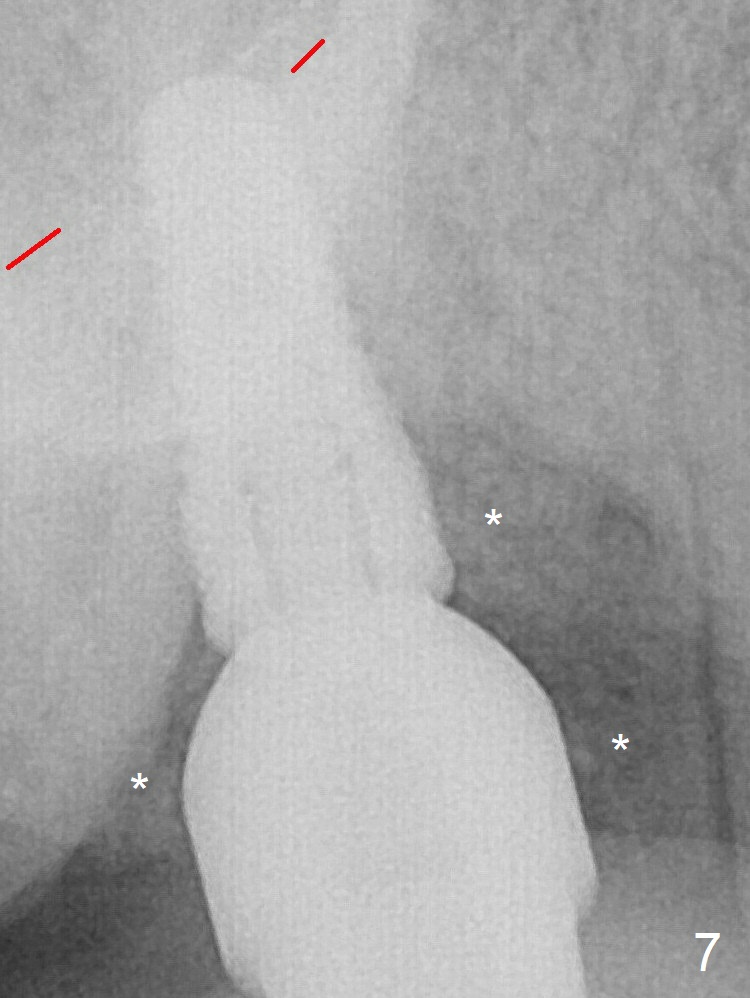

The 4.5x10 mm SM implant appears to have penetrated the sinus floor for primary stability (Fig.7 red dashed line).  *: bone graft around the coronal portion and the implant and the apical portion of the abutment (6.8x5.5(6) mm).  There is no loss of bone graft 3 months postop (Fig.16 (abutment: 4.8x7(4.5) mm)).